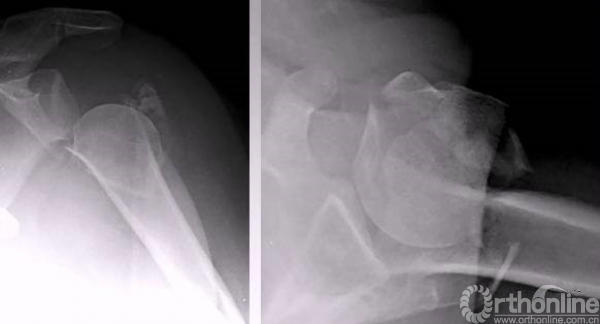

病例1

4部分骨折

正位的翘拨复位

腋位的翘拨复位